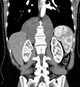

Pneumomediastinum with retroperitoneal extension

Abnormal left upper quadrant abdominal gas collection

Abnormal right upper quadrant abdominal gas collection